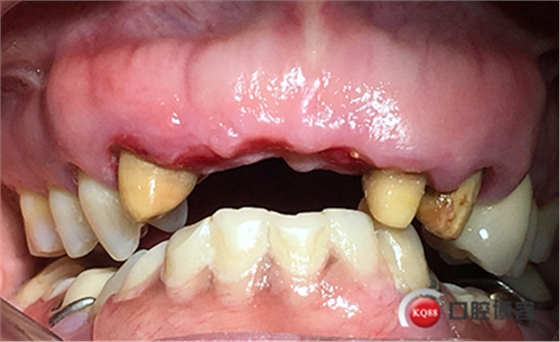

患者女性,52歲,缺失三顆牙,骨性前突,頜弓窄,身高175,魁梧,放了三顆牙是不是有點細?左上3開膠了,牙體有腐蝕。

設計:1.僅做牙槽嵴頂水平切口,不做垂直切口,2.缺牙區(qū)由三顆牙改成兩顆牙,3.鄰牙冠延長。